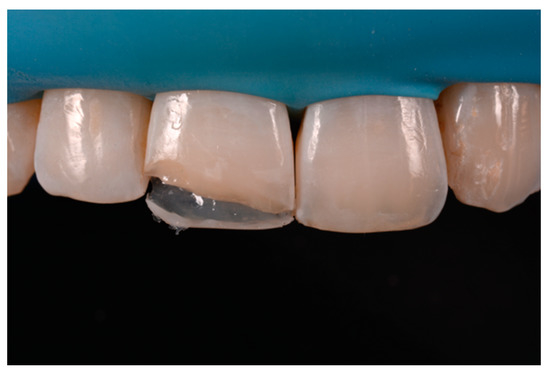

Figure 24.

Frame is corrected with the help of diamond burs. Reprinted from Restauri diretti nei settori anteriori, G. Paolone, S. Scolavino, © 2021, with permission from Quintessence Publishing Italy.